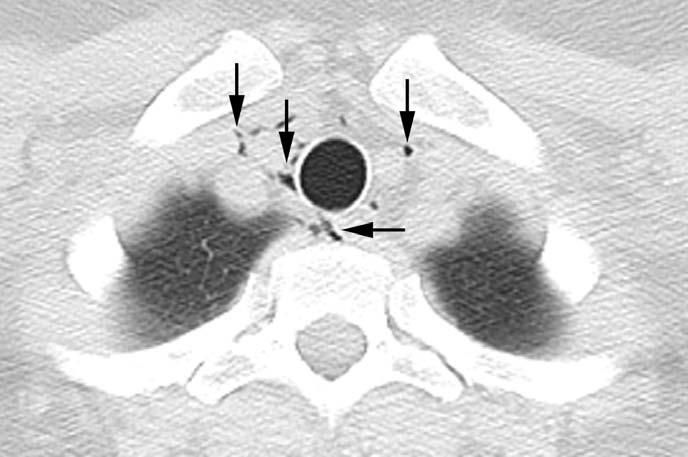

A chest radiograph was obtained for further assessment and is shown left (Figure 2).

The patient's CT scan of the chest demonstrated small collections of gas in the mediastinum, consistent with pneumomediastinum (Figure 1). The chest radiograph showed a large amount of free air below both hemidiaphragms (Figure 2). Cardiac and mediastinal contours were within normal limits. The lungs were clear, and there was no pleural effusion.

Figure 2 – A large amount of free air under the diaphragm (arrows) can be seen in this portable chest radiograph obtained in the emergency department.